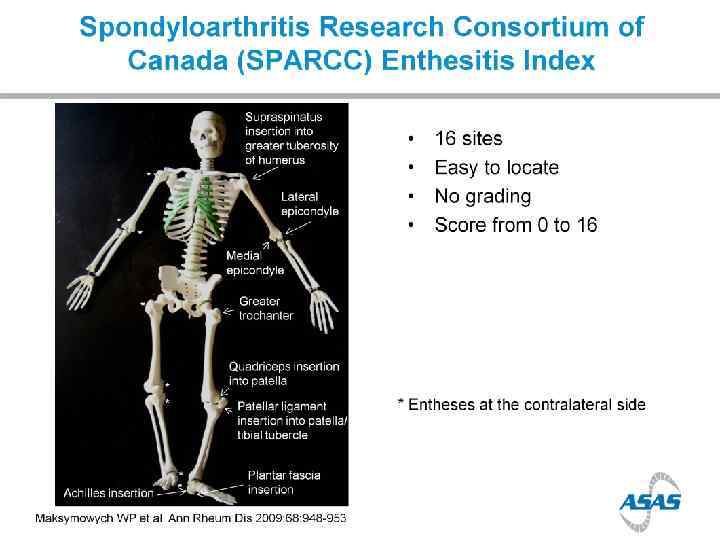

Enthesopathy

Enthesopathy

Enthesopathy